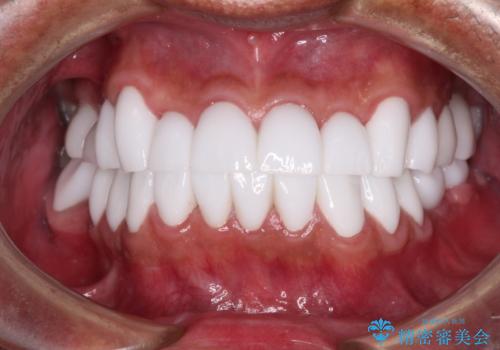

本来、あまりにも不自然な歯となるため、フルジルコニアクラウンを前歯に使用することは、咬合力が強すぎる場合を除き、ほとんどありません。

それでも、色調、形態ともに不自然なくらい真っ白な歯をご希望でしたので、患者様には大変満足していただきました。